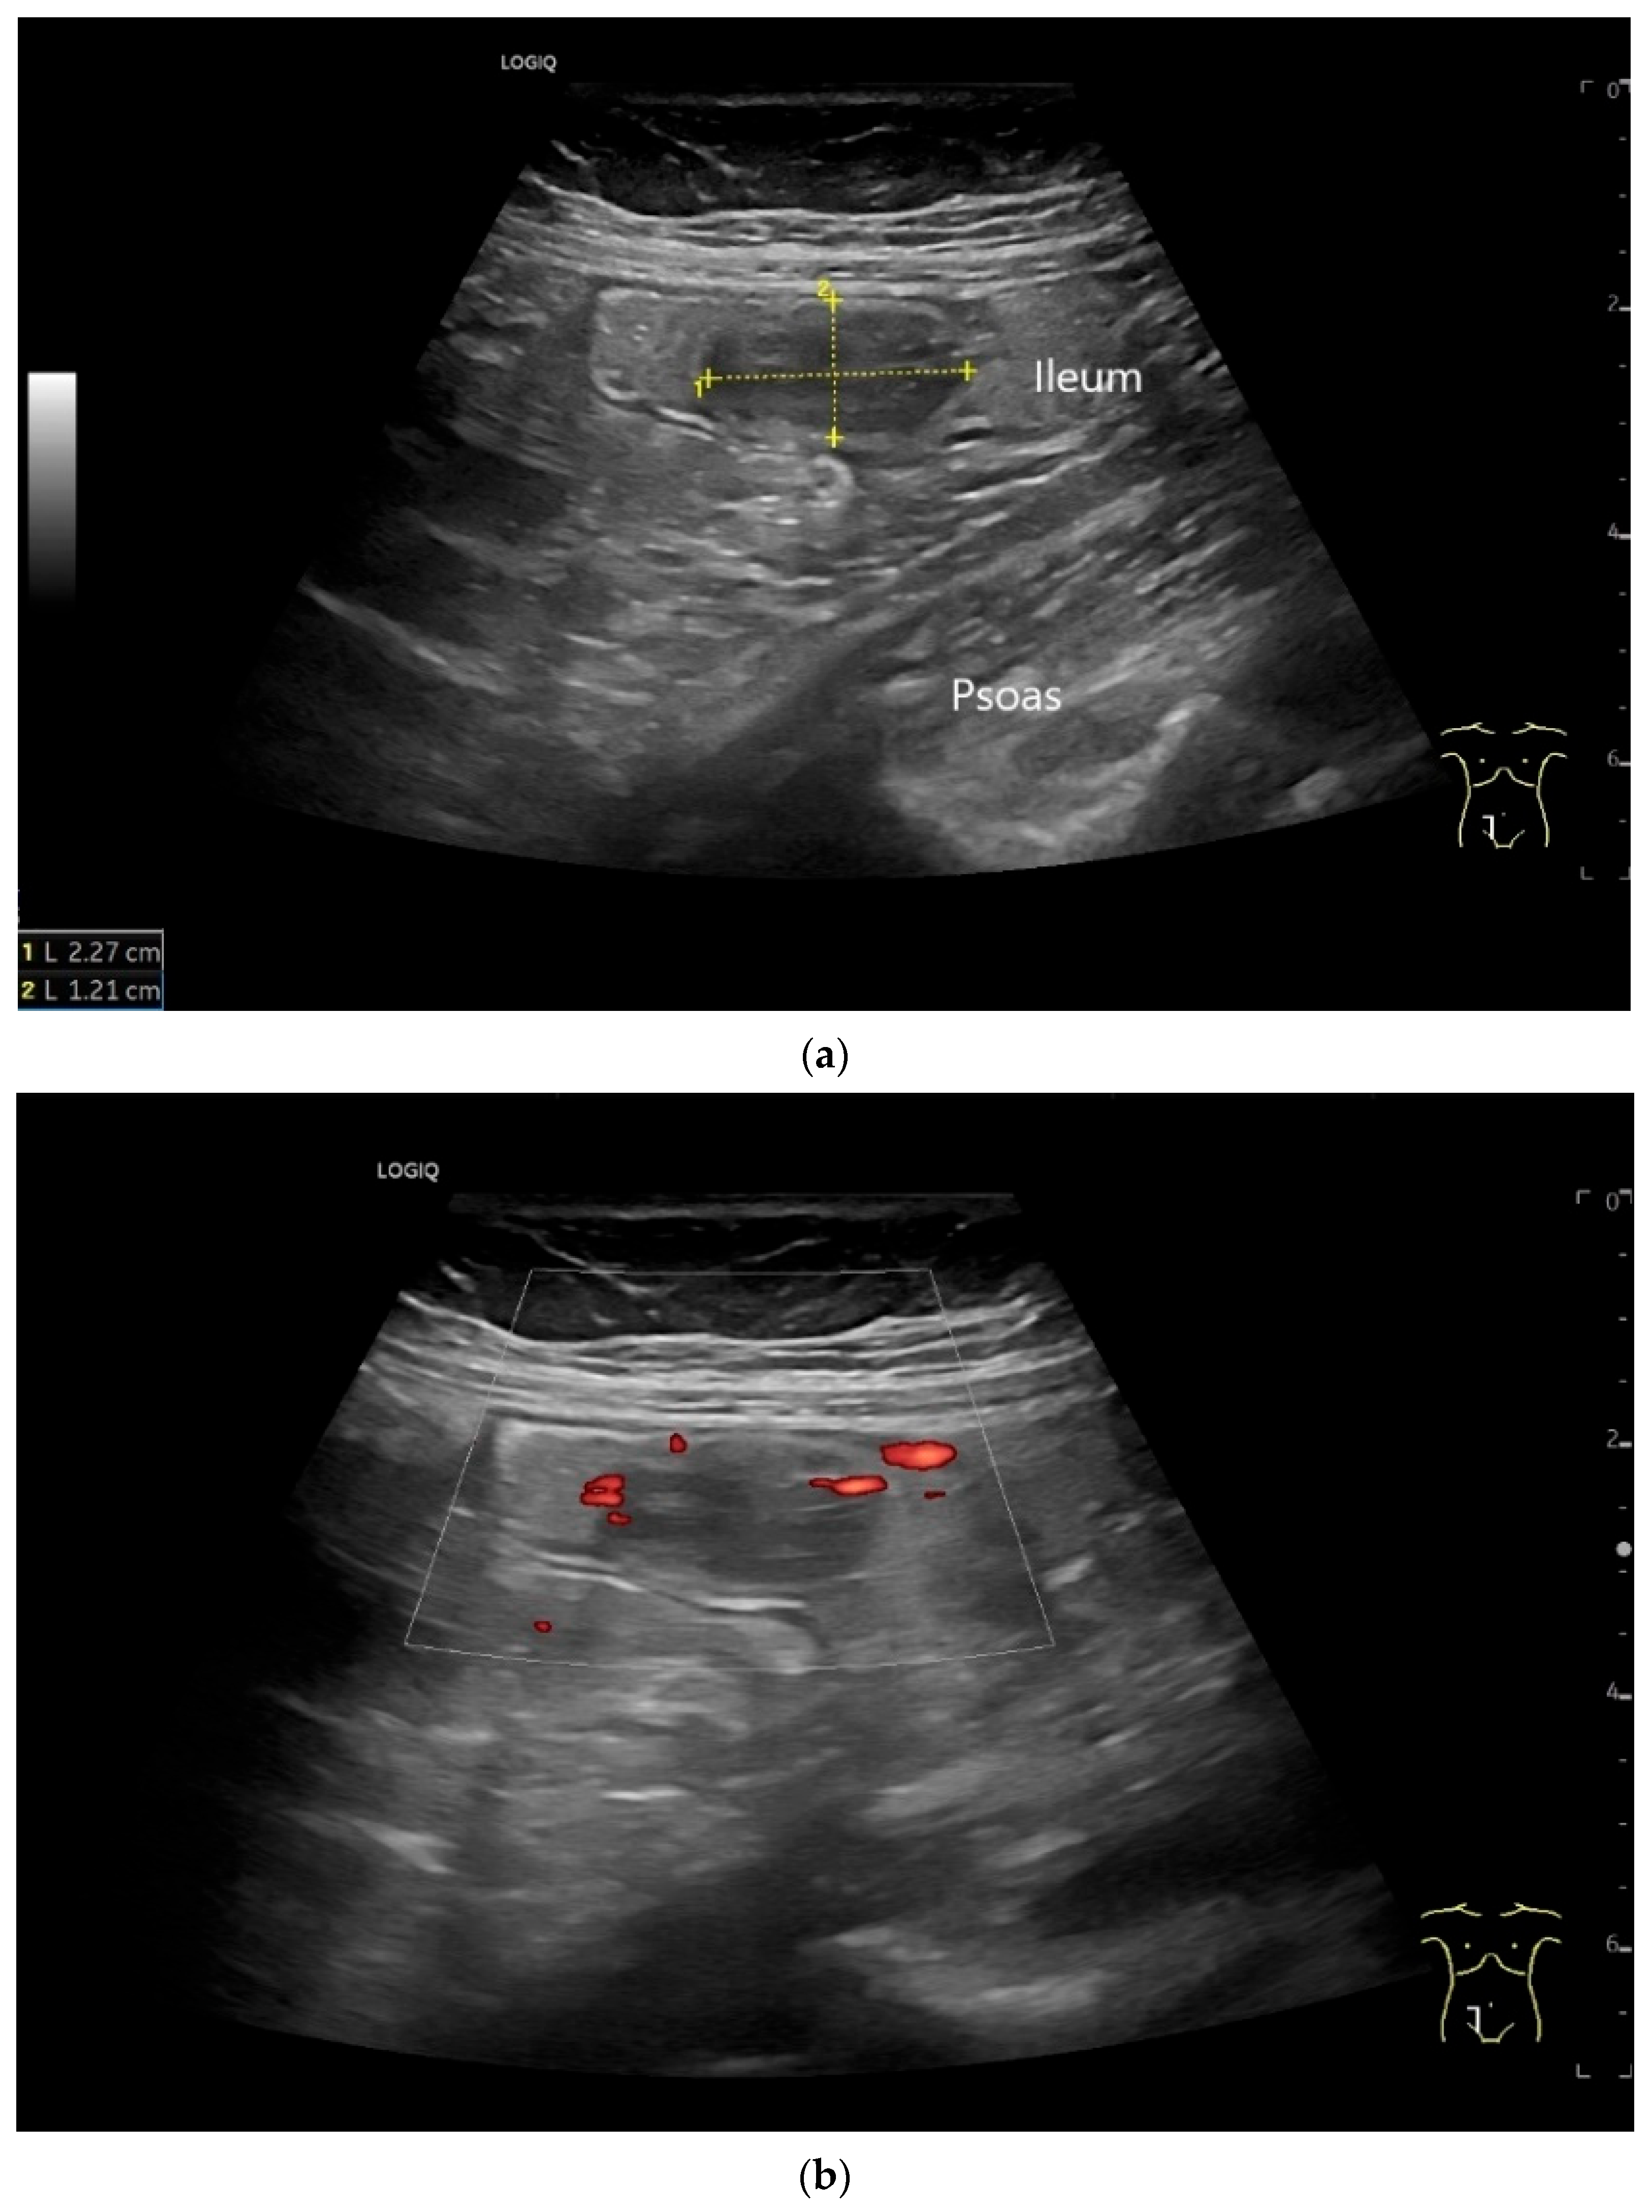

| Neuroendocrine tumor | Small, nodular hypoechoic wall thickenings, mostly in the submucosa with spreading into the other layers. Usually with small vessels on CDI. Regionally enlarged lymph nodes. Multilocular manifestations are possible. |

| GIST | Round hypoechoic masses, homogeneous or heterogeneous depending on size. They usually originate from the muscularis propria, which can be difficult to distinguish in US. Small vessels on CDI, hyperenhancement on CEUS. They move with the small intestine and can change position. |

| Proximal to the tumor | Dilated small bowel lumen, possibly hypertrophy of the muscle layer and hyperperistalsis of this bowel segment |